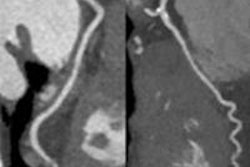

The conference will include sessions on imaging the coronary arteries with CT, current and future applications of cardiac nuclear medicine, triple rule-out CT, and assessing myocardial perfusion with CT, the RCR said.